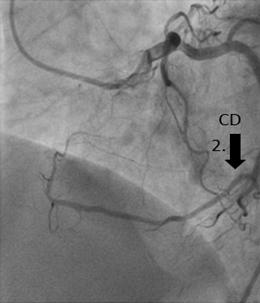

Origen anómalo congénito de la coronaria derecha a partir de la arteria circunfleja distal